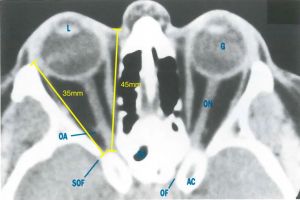

The average dimensions of the orbit are as follows:[2]

| Height | 35mm |

| Width | 40mm |

| Length of the medial orbital wall | 45mm |

| Length of the lateral orbital wall | 35mm |